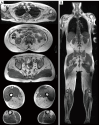

Axial Dixon FF images of a healthy 26-year-old male with a BMI of 23 kg/m2 (within the healthy weight range of BMI 18.5 to <25 kg/m2), showing non-segmented (A) and segmented (B) images; and a healthy 31-year-old male with a BMI of 27 kg/m2 (within the overweight range of BMI 25.0 to <30 kg/m2), displaying non-segmented (C) and segmented (D) images. The male with overweight (C,D) exhibited myosteatosis with higher values of IMAT and FF in both flexor (red) and extensor (blue) compartments compared to the healthy weight male (A,B). FF, fat fraction; BMI, body mass index; IMAT, intermuscular adipose tissue.